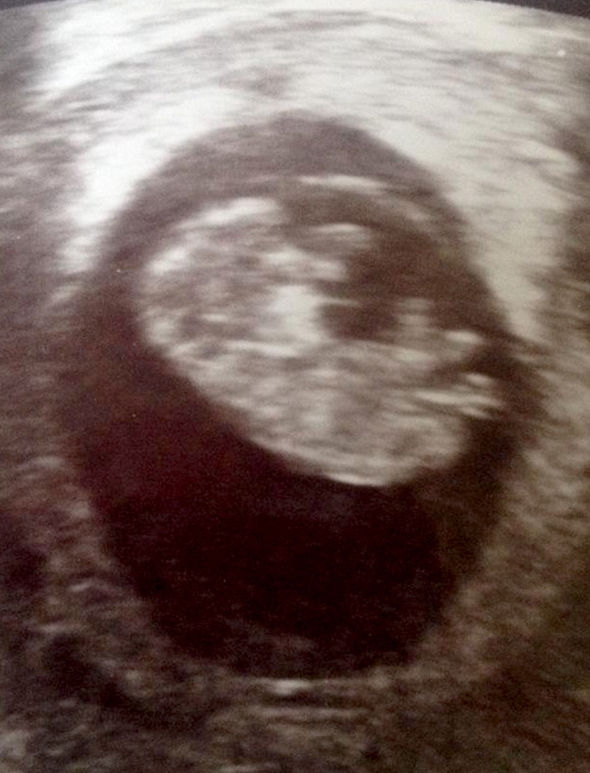

08/11/2017 17:24Thai phụ vỡ tử cung, đứa trẻ suýt “chết đuối” trong bụng mẹ vì một biến chứng nguy hiểm

Sau khi sinh hai đứa con gái, vợ chồng chị Claire và anh Matt Gaylor được bác sĩ thông báo rằng chị gặp phải hội chứng Asherman - các mô sẹo hình thành trên tử cung, hay còn gọi là hội chứng dính tử cung. Tình trạng này có thể dẫn đến vô sinh, sẩy thai, đau đớn và các biến chứng hậu sản trong tương lai như chứng lạc nội mạc tử cung. Bác sĩ cũng cho biết, Claire và Matt sẽ rất khó tiếp tục có con sau này.

Cũng chính vì vậy, có thể tưởng tượng được bao nhiêu ngạc nhiên và mừng rỡ khi cặp đôi phát hiện ra Claire lại mang thai thêm lần nữa vào năm 2013. Bên cạnh niềm hạnh phúc đón chờ đứa con, Matt và Claire vẫn chưa bao giờ yên lòng vì nỗi sợ hội chứng Asherman sẽ gây những ảnh hưởng đến đứa bé trong bụng.

27 tuần thai của Claire trôi qua êm ả, sức khỏe của mẹ bầu và thai nhi đều rất tốt. Claire và Matt vẫn tưởng rằng họ đã sắp vượt qua được thử thách của những tuần thai khó khăn để đón chào một đứa con khỏe mạnh. Không ngờ đến tuần thứ 28, Claire đột nhiên gặp phải những cơn đau kinh khủng ở vùng bụng trên và ngực. Claire đã được bác sĩ chẩn đoán bị ợ nóng và điều trị bằng thuốc uống giảm đau trong suốt 10 ngày trời.

Tuy nhiên tình trạng của Claire chẳng thuyên giảm chút nào. Khi cơn đau đớn hành hạ càng tệ hơn, Claire lập tức được chuyển vào phòng sinh và cô đã rơi vào hôn mê ngay sau đó. Các bác sĩ lúc này mới nhận thấy được tình trạng của Claire rất nghiêm trọng.

Họ tiến hành kiểm tra kỹ hơn và bàng hoàng nhận thấy rằng, những cơn đau của Claire không chỉ đơn giản là do cô mắc chứng ợ nóng mà sản phụ này đã gặp đã bị nhau cài răng lược dạng percreta. Đây là một tình trạng hiếm gặp và cực kỳ nguy hiểm khi bánh nhau bám quá sâu vào thành tử cung. Trong trường hợp của Claire, bánh nhau đã ăn xuyên qua lớp tử cung khiến tử cung bị vỡ ra.

Claire bị hôn mê suốt 5 ngày trời, trong khi đó bé Cody sau khi ra đời đã phải trải qua hai lần thực hiện hồi sức tim phổi vì bé đã nuốt phải quá nhiều máu của mẹ khi ở trong tử cung. Người chồng đáng thương Matt gần như tuyệt vọng khi hai mẹ con Claire từng giờ từng phút phải giành giật lại sự sống.

Thật may mắn, nhờ sự can thiệp bằng biện pháp sinh mổ kịp thời, bác sĩ cũng đã tiến hành cắt bỏ tử cung của người mẹ, cuối cùng cả hai mẹ con Claire đều đã vượt qua được cửa tử thật kỳ diệu.

“Chỉ cần chẩn đoán chậm vài giờ thôi, có lẽ tôi đã không giữ được mạng sống. Khi tôi tỉnh dậy, bé Cody đã ra đời. Thật không thể tin được chúng tôi đã vượt qua được cái chết cận kề đến như vậy”, chị Claire chia sẻ. “Đã có lúc Matt gần như phải nói lời tạm biệt với tôi và Cody. Anh ấy đã phải trải qua những thời khắc thật kinh khủng”.

Thực tế, ngay cả bác sĩ cũng rất bất ngờ trước sự thoát chết ngoạn mục của hai mẹ con Claire và Cody. Họ đã dùng chính tư liệu về trường hợp của Claire để làm tài liệu đào tạo cho các bác sĩ chẩn đoán và chữa trị cho thai phụ bị nhau cài răng lược.

Cody giờ đây đã là một cậu bé 3 tuổi khỏe mạnh và xinh xắn. Cậu bé đã trở thành động lực để Claire tham gia vào tổ chức gây quỹ, đóng góp vào việc nghiên cứu về chứng nhau cài răng lược cũng như hoạt động tuyên truyền nâng cao nhận thức của phụ nữ, thai phụ về chứng bệnh nguy hiểm này.